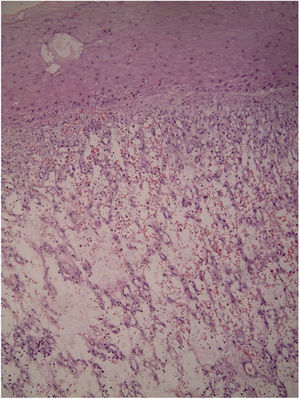

Relato de casoRelatamos um paciente do sexo masculino, 45 anos, portador de espondilite anquilosante, em uso de adalimumabe havia cinco anos. Há quatro meses, notou pápula eritematosa em antebraço direito, que evoluiu com tumoração vegetante, de crescimento rápido, friável, de coloração vermelha, com cerca de 4,5cm de diâmetro (figs. 1 e 2). Queixava‐se de dor e episódios de sangramento espontâneo. Foi feita a exérese da lesão. Exame histopatológico mostrou nódulo ulcerado. Na derme superficial, havia proliferação de pequenos vasos e intenso infiltrado inflamatório de neutrófilos com deposição de fibrila, além de células gigantes de corpo estranho que fagocitavam material exógeno refringente. Na derme profunda, proliferação de vasos capilares dilatados em meio a infiltrado inflamatório plasmocitário e histiocitário, compatível com hemangioma capilar lobular (figs. 3 e 4). O paciente mantém o uso de adalimumabe sem surgimento de novas lesões.